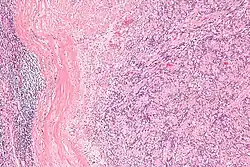

| Micrograph of an intranodal palisaded myofibroblastoma. H&E stain. | |

IPMs are diagnosed by examination of the tissue by a pathologist. They have a rim of peripheral lymphoid tissue (remnant of a lymph node) and consist of spindle cells with nuclear palisading. Red blood cell extravasation is common and blood vessels surrounded by collagen with (fine) peripheral spokes (amianthoid fibers) are usually seen.[2]

Immunostains for smooth muscle actin and cyclin D1 are characteristically positive. The main histologic differential diagnosis is schwannoma.

Low mag. -